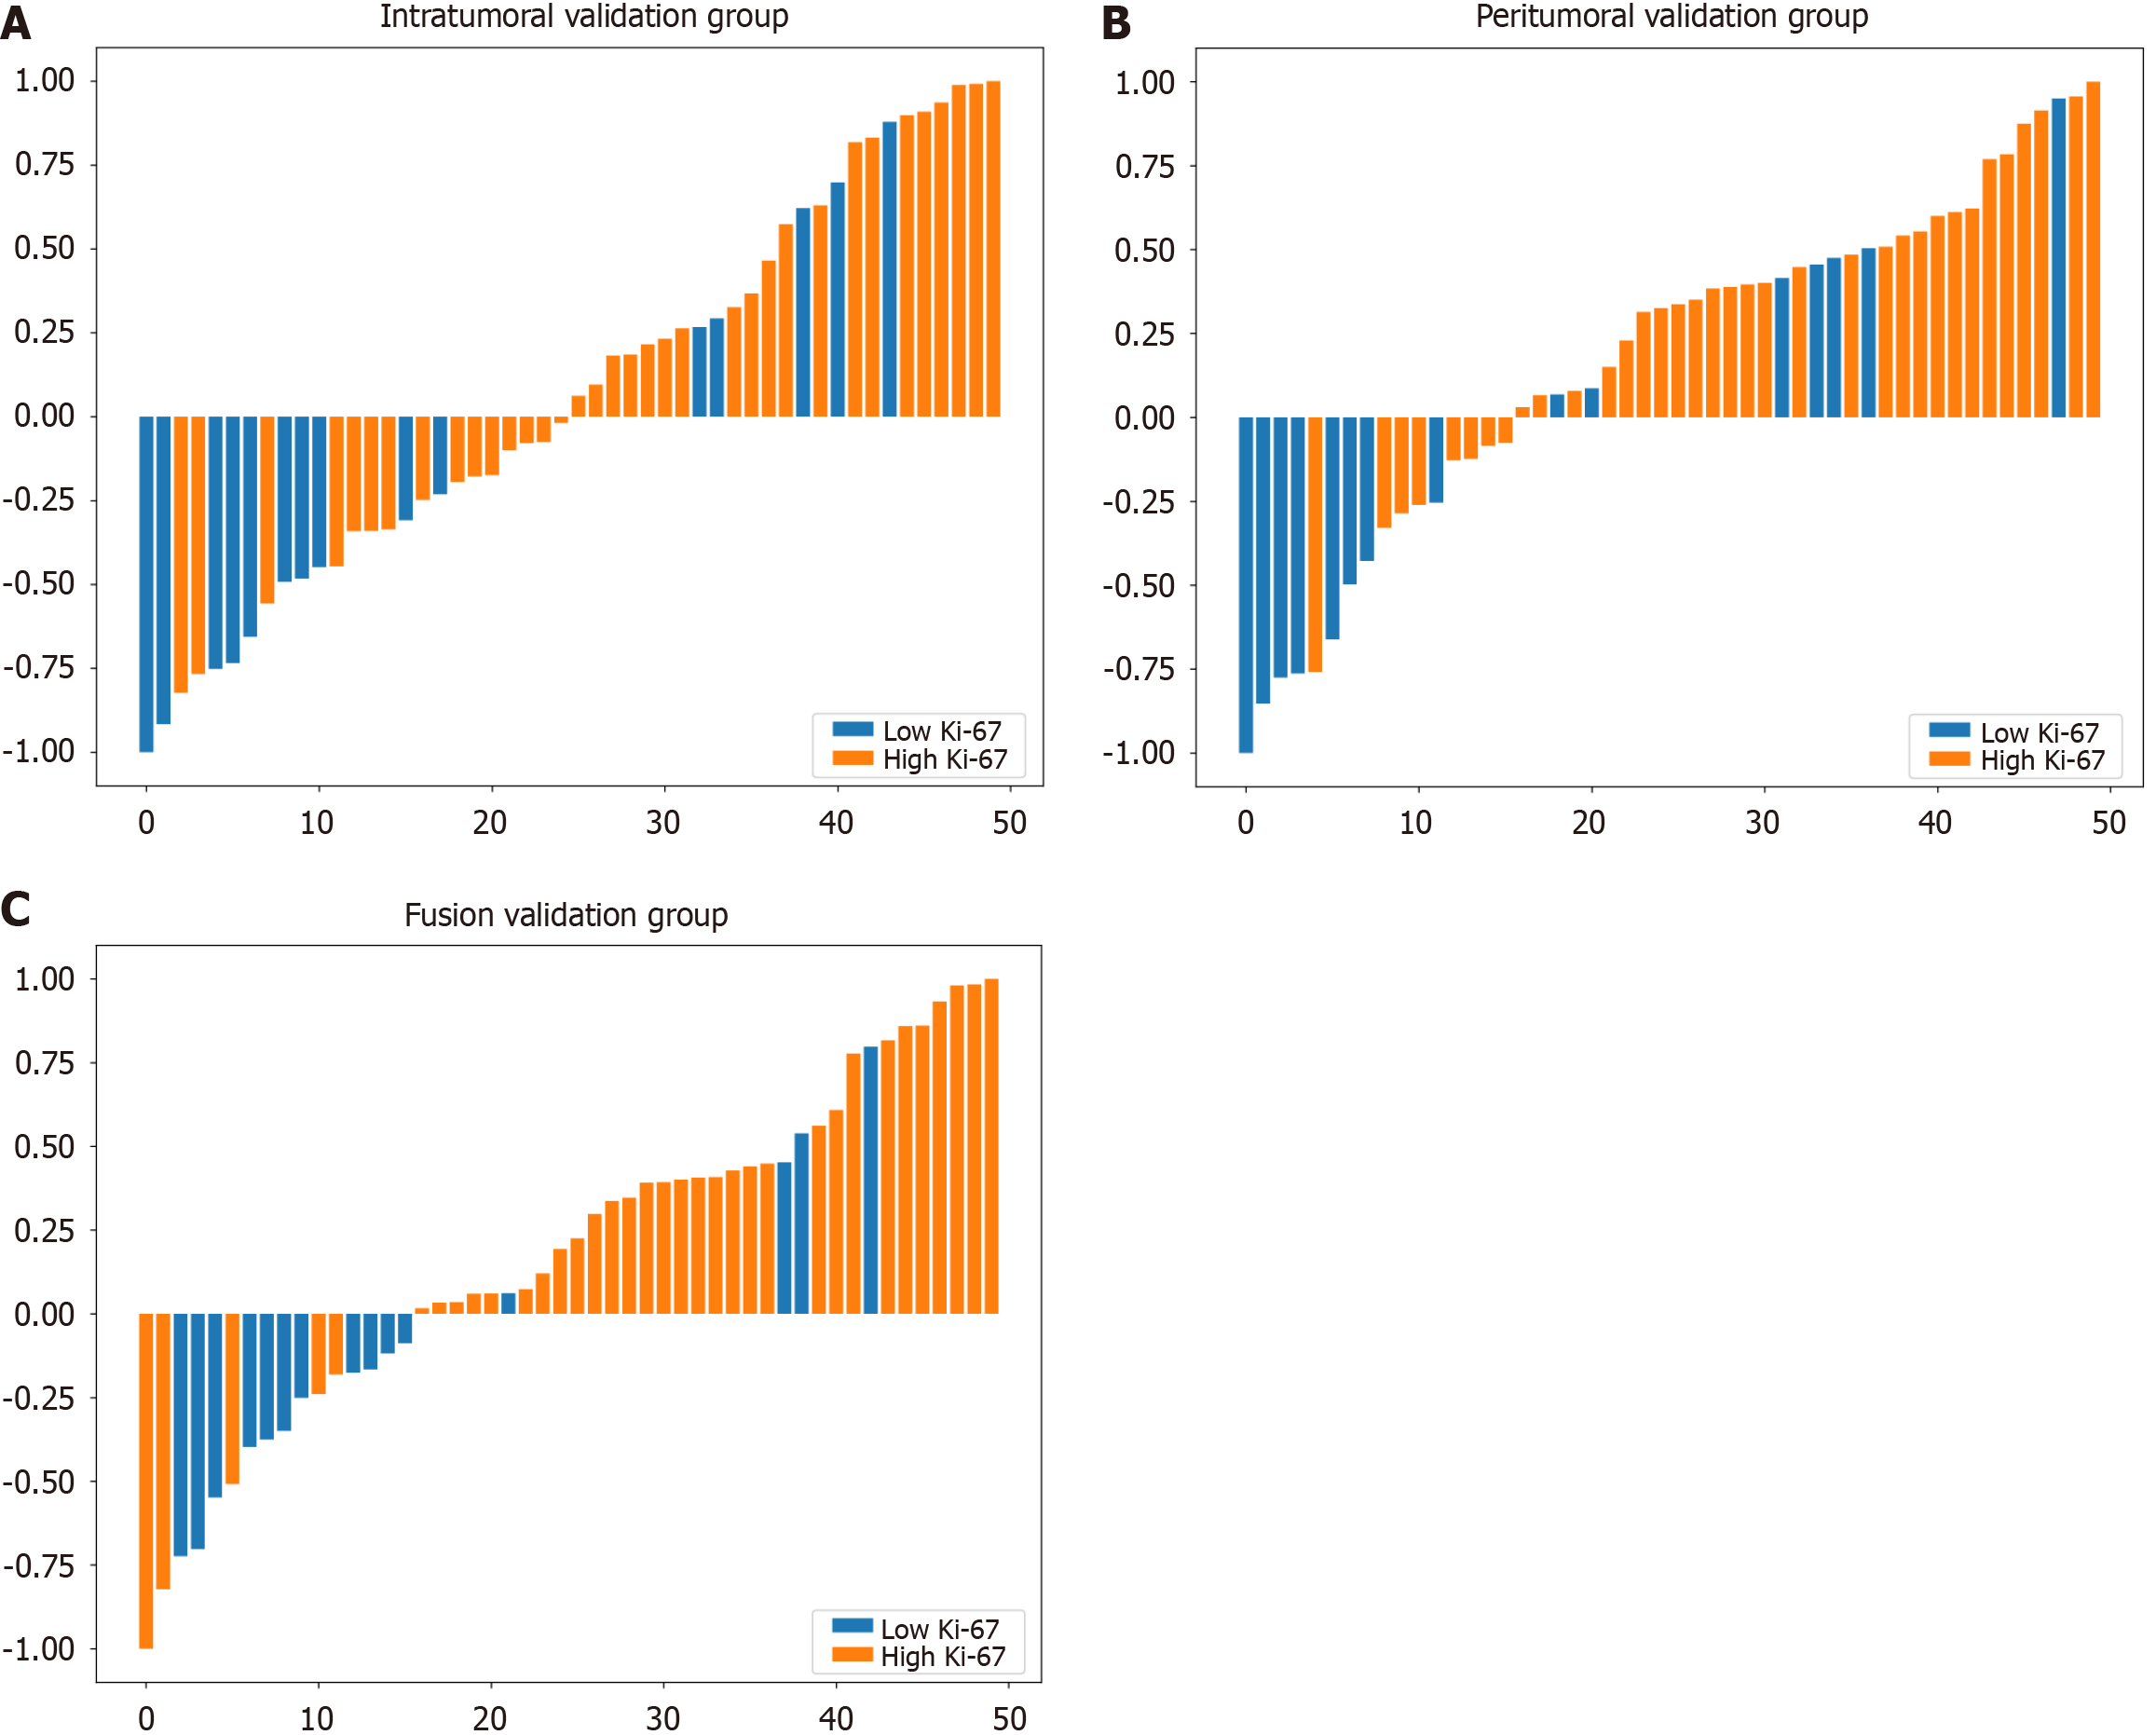

Using the logistic regression algorithm, we constructed predictive models and selected the best-performing model. Among the three models in the validation group, the fusion model had the highest predictive capability, with an AUC of 0.760 (0.601-0.919), which surpassed those of the intratumoral model [AUC of 0.703 (0.526-0.880)] and the peritumoral model [AUC of 0.716 (0.541-0.892)], as shown in Figure 4. The ROC curve for the training group is presented in Supplementary Figure 4. To further demonstrate the performance of the model, we plotted waterfall plots for each of the three prediction models. The results showed that the three models have high accuracy in assessing the expression level of Ki-67. The waterfall plot of the validation group is shown in Figure 5, and the waterfall plot of the training group is shown in Supplementary Figure 5.